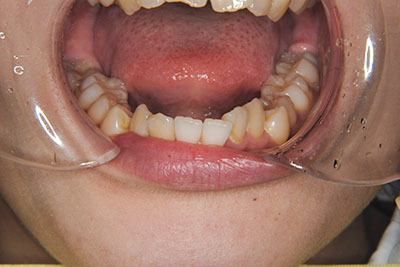

おとなの方でも矯正治療をあきらめないでください!

子供の頃に矯正治療を行う方が治療期間が短く済むというのは、確かですが、矯正治療は患者様の意識も重要です。

いくら歯が動き易くとも、本人がやる気でなければ効果は出ませんし、むし歯発生のリスクも高まります。おとなの方は顎の成長が終わっているため、治療の計画が立てやすいとも言えます。「もう大人だから…」とあきらめず、一度ご相談ください。